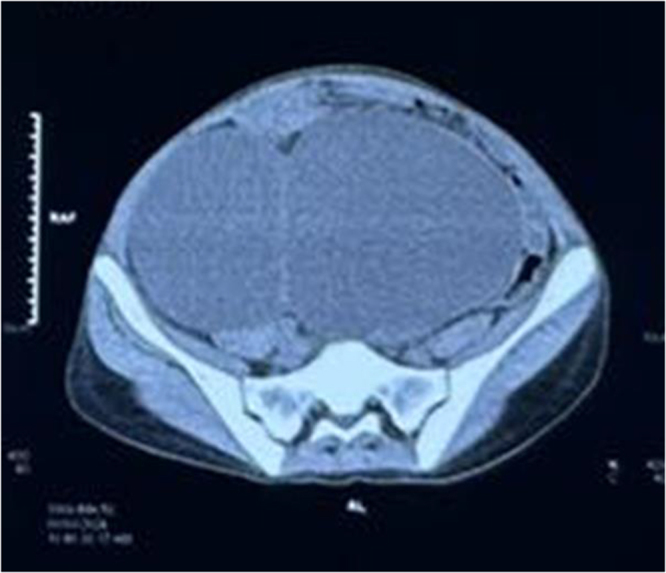

Case presentation: An 18-year-old female with stage V chronic kidney disease developed abdominal distension and bowel obstruction caused by a large renal cyst. Imaging confirmed the diagnosis, and conservative management with fluid control, dialysis, and infection management was initiated.

Discussion: The presentation of a renal cyst causing bowel obstruction is extremely rare, and the optimal management approach remains unclear. Diagnosis relies on imaging modalities such as ultrasound and CT, which help identify cyst characteristics and associated complications. In such cases, conservative treatment is generally preferred, focusing on symptom management through dietary modifications, while surgical intervention is considered only if symptoms persist despite medical therapy.